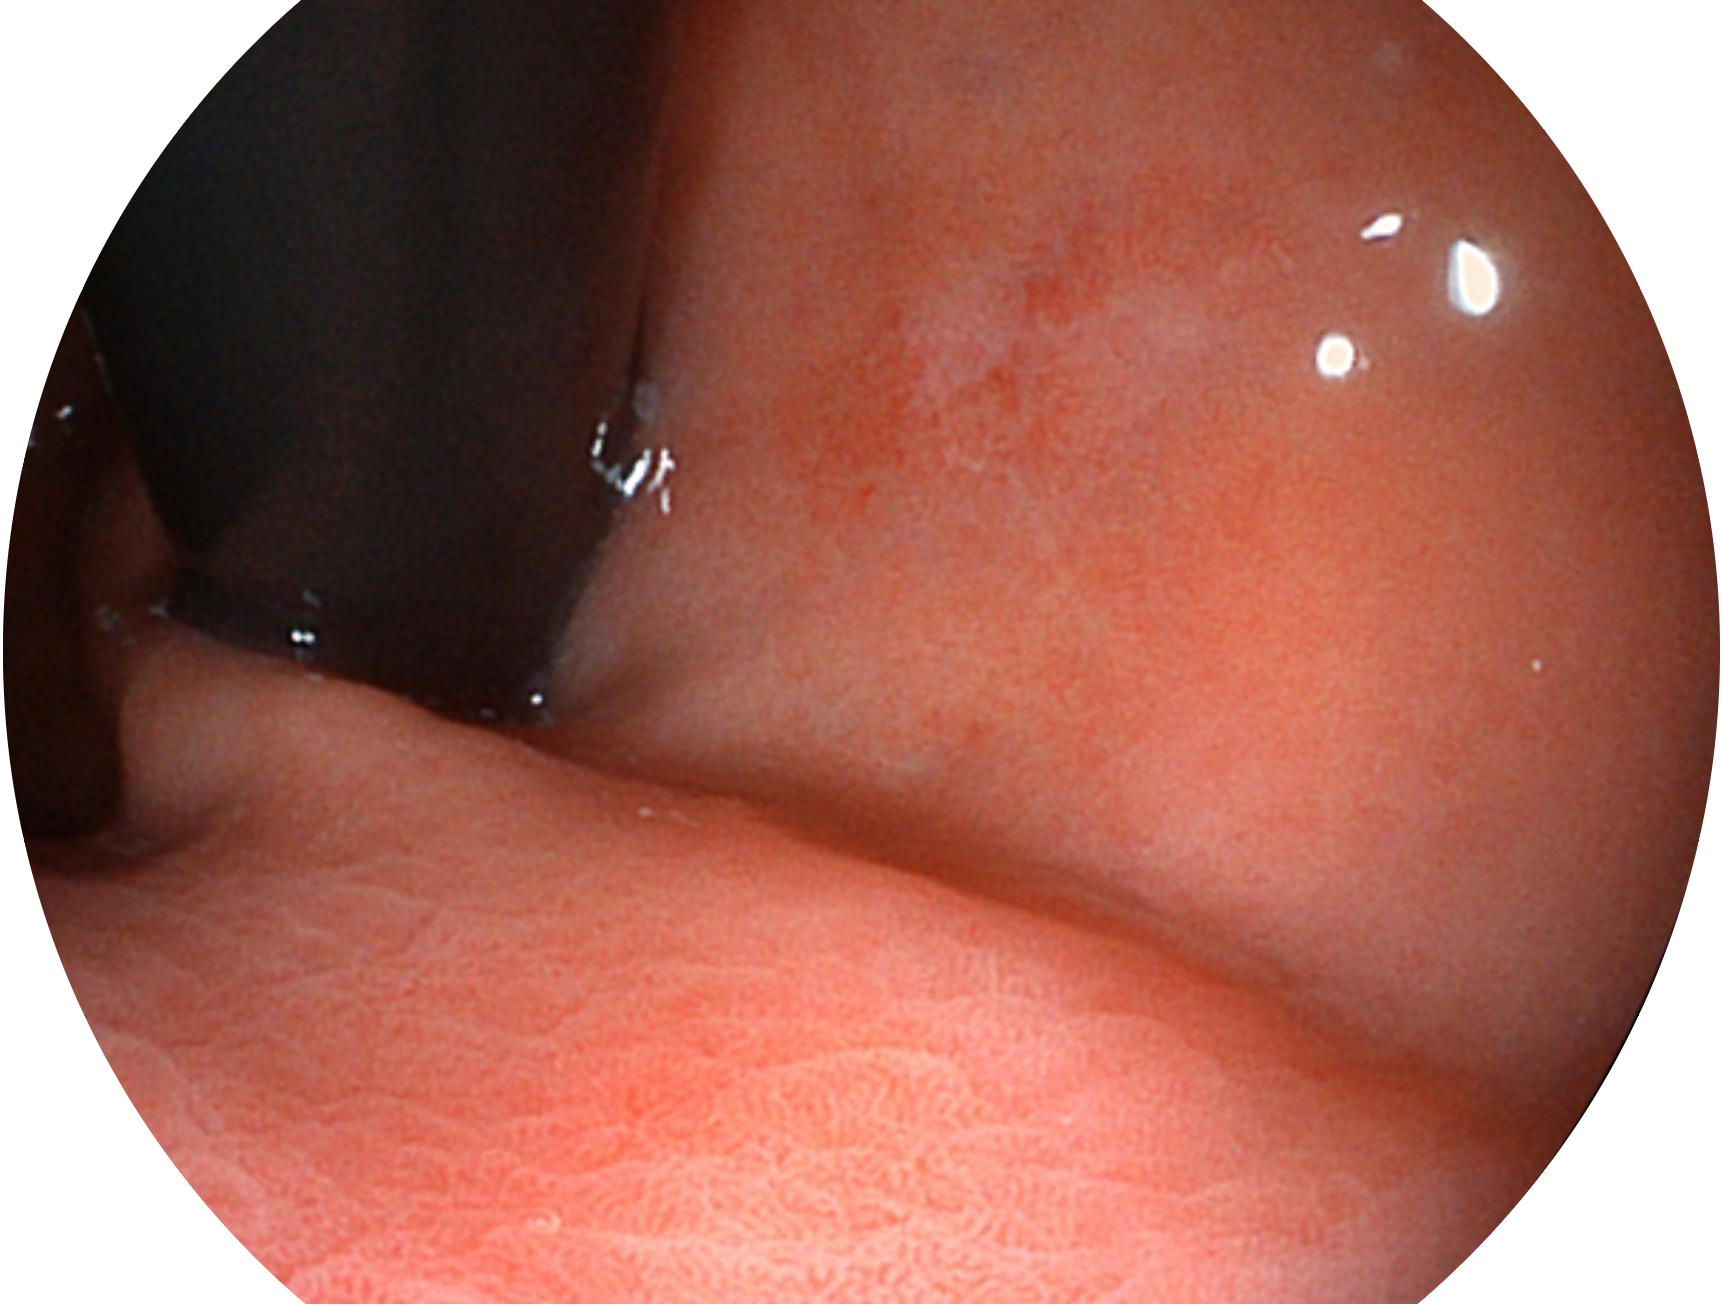

玖鼎集团新开发的内镜染色技术,主要是基于多波长LED 光源的开发,VLS-55Q 四波长LED 光源是由四个不同颜色的LED光按照相应照明模式所规定的特定发光比例进行合束后形成,合束后形成的照明光的光谱由红光、绿光、蓝光及蓝紫光这四个不同的波段范围构成。具有更高光谱自由度,通过光谱比例的控制,实现了聚谱成像技术,英文全称为“Spectral Focused Imaging, SFI”,缩写为“SFI”和光电复合染色成像技术,英文全称为“Versatile Intelligent Staining Technology, VIST”,缩写为“VIST”。